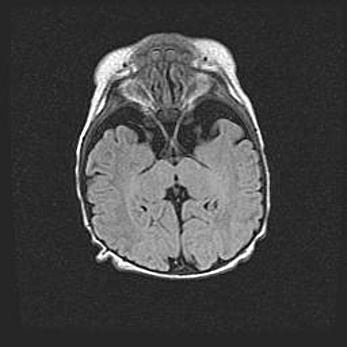

Наружная гидроцефалия с возможной атрофией височных областей.

Возраст: 28 дней

Вес: 3670 г

Пол: мужской

Окружность головы: 38 см

Срок гестации: 40 недель

Гидроцефалия головного мозга у новорожденных – это заболевание, которое характеризуется скоплением избыточного количества спинномозговой жидкости в желудочковой системе головного мозга в результате затруднения её перемещения от места выработки к месту поглощения в кровеносную систему или вследствие нарушения абсорбции. При открытой наружной форме гидроцефалии у новорожденных расширяются и переполняются субарахноидные пространства.

При нормотензивных  формах,  которые,  как  правило,  являются  следствием  перенесенных ишемических  повреждений  паренхимы  мозга,  возможно  сочетание микроцефалии  с нормотензивной гидроцефалией. В основе данных изменений лежит атрофия больших полушарий с преимущественной  локализацией  в  лобно-височных  областях.